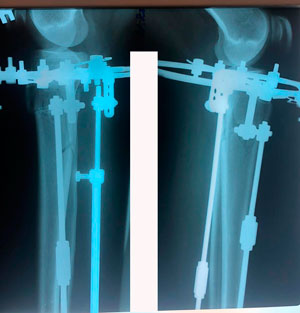

рентген перед фиксацией

image-04-08-20-02-07-1.jpg

image-04-08-20-02-07.jpg